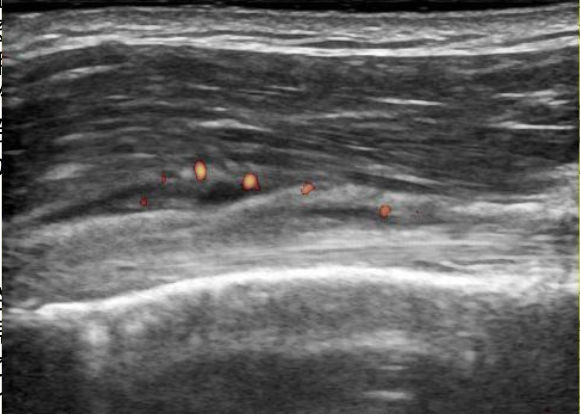

超音波検査について

リウマチ科領域では超音波診断の有用性が認識され、日常診療でも広く普及しつつあります。リウマチ性多発筋痛症においても超音波検査を用いた診断を実践していますが、多くの画像所見は特徴的ではあっても疾患特異的(すなわち確定診断の根拠となる)所見ではないため、症状を有する部位の観察のみで診断が得られることはまずありません。

他の疾患を正しく鑑別するためには、

- 症状を有する部位以外の画像所見の評価

- 他の臨床情報も十分加味

- 必要に応じて関節穿刺を行い貯留した液体の評価